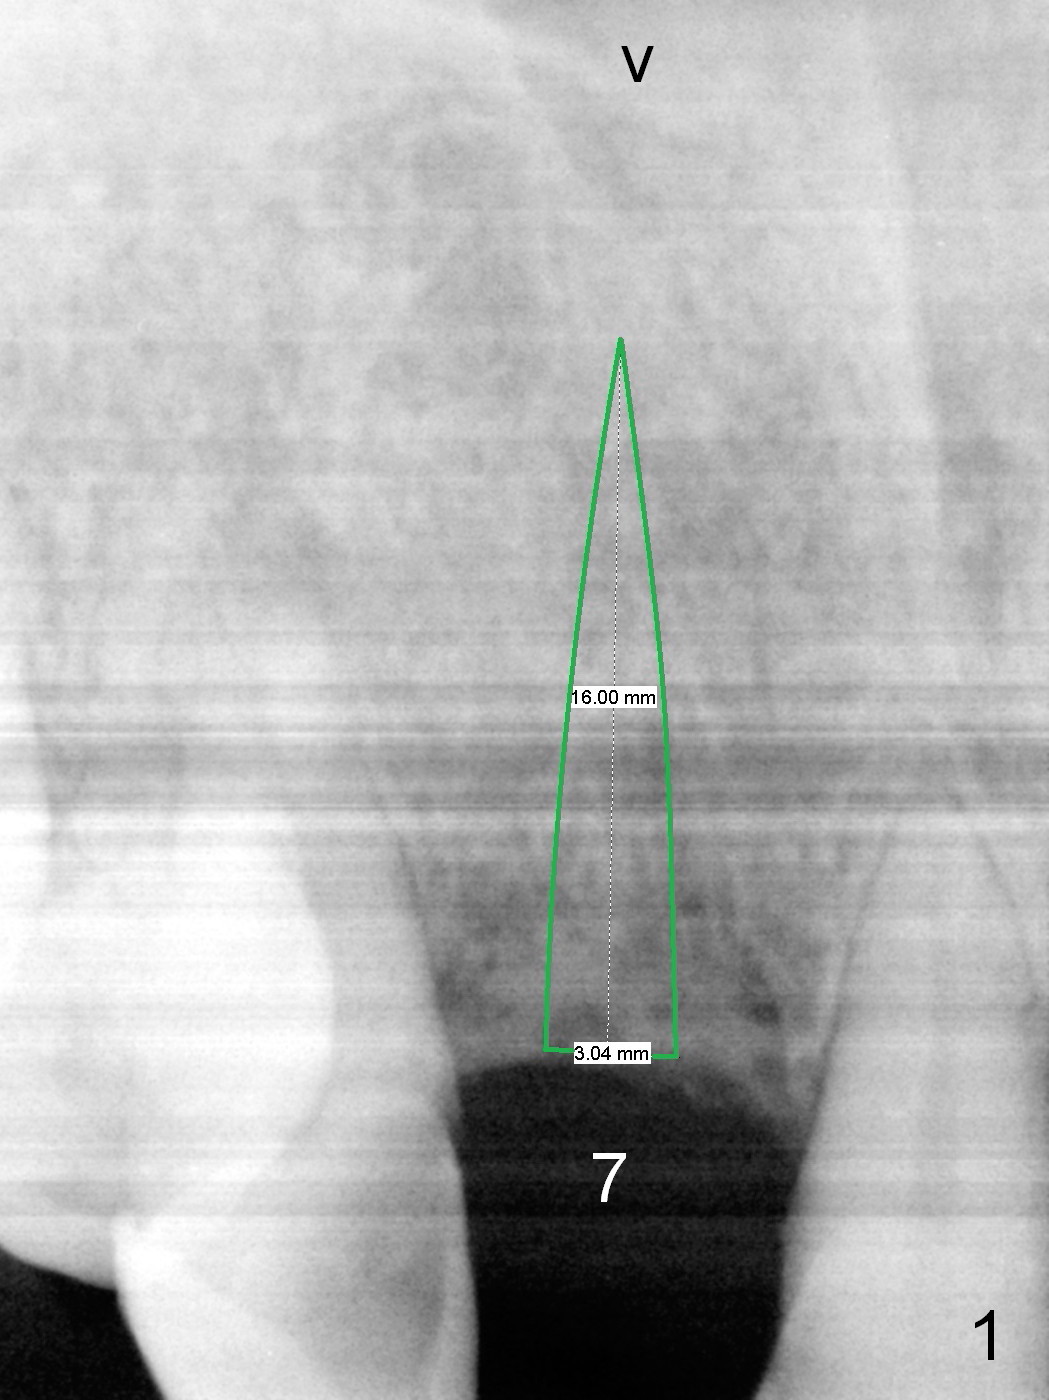

Implant placement at #31 reveals that bone width (bucco-lingual) is not a problem for a 64-year-old man. He requests implant placement at #7 and 14 (Fig.1,3), because the upper flipper has been lost. He wants to make sure that the implant at #7 does not cause the pain at #6. In fact the flipper appears to have lead to caries (Fig.2 *) and periapical radiolucency (<) at #6. RCT is rendered at #6 prior to a 1-piece implant at #7 (Fig.1). Since bone height is sufficient, the implants do not have to penetrate the nasal floor (Fig.1 v) or the sinus floor (Fig.3 <) unless the bone density is low. Prepare implant positioner of 4 mm to determine whether the ridge is wide to hold a 3.8 or 4 mm implant. Take preop photos to show the ridge width.